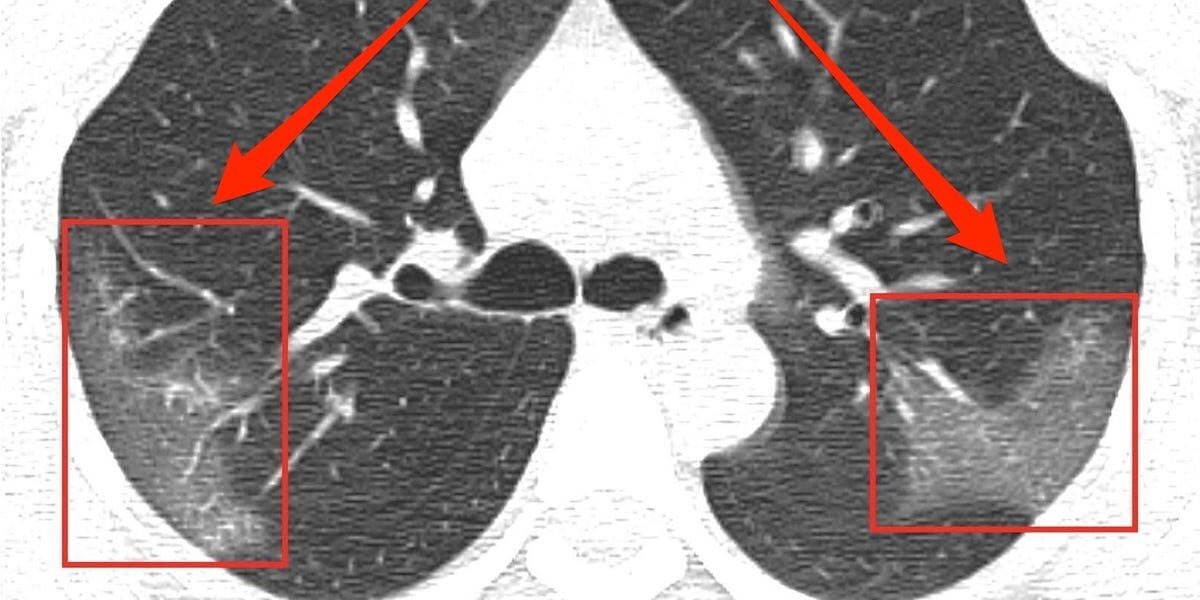

Как протекает коронавирусная пневмония мы можем видеть на снимках компьютерной томографии органов грудной клетки, пример:

Симптом "матового стекла" при коронавирусной пневмонии (фото из сети интернет)

Имеем признак "матового стекла", что якобы характерно для коронавирусной пневмонии.

Поэтому очаги "матового стекла" при коронавирусной пневмонии локализуются по периферии легких, а не как при классической бактериальной инфекции или вирусной инфекции - в прикорневой части легких и в нижних отделах легких. Это похоже на кипение жидкости в легких, которая пытается выйти наружу из грудной клетки. Кстати, один из симптомов - это повышенная потливость больных коронавирусом!